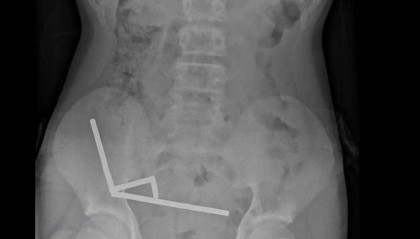

腹痛4天后送医,新西兰男孩吞下约100颗磁铁致肠道坏死 医生切除部分肠组织

近日,新西兰一名13岁男孩吞下多达100颗在网上购买的大功率磁铁,接受了手术将其取出。医生表示,手术...